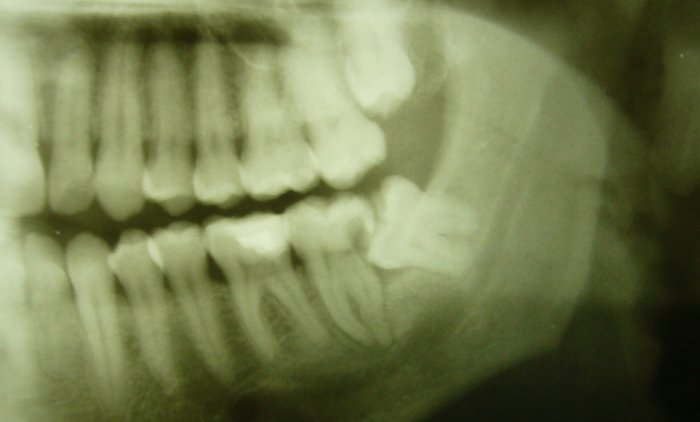

Zu den häufigsten zahnärztlich-chirurgischen Eingriffen gehört die Entfernung verlagerter Weisheitszähne. Da diese Zähne als letzte durchbrechen finden sie meistens nicht genügend Platz im Kiefer, bleiben auf halbem Weg stecken (siehe Bild) und verursachen eine Reihe von ernsten Problemen, die oft mit starken Schmerzen verbunden sind. Auch hier ist wieder Vorbeugung das Mittel der Wahl. Wenn aufgrund des Röntgenbefundes Weisheitszahnprobleme zu erwarten sind, werden wir die prophylaktische Entfernung immer empfehlen noch lange bevor die ersten Beschwerden auftreten. Eine Kieferoperation verläuft meist wesentlich besser, wenn das Operationsgebiet noch nicht entzündet ist. Normalerweise entfernen wir in einer Sitzung die beiden Weisheitszähne auf einer Seite. In der Regel dauert eine Weisheitszahnoperation nicht länger als 20 Minuten. Auf Wunsch können wir auch alle 4 Weisheitszähne auf einmal entfernen.

Im nebenstehenden Bild können Sie sehr eindrucksvoll sehen, wie sich an dem vor dem unteren Weisheitszahn gelegenen Zahn 37 ein enorm großer kariöser Defekt (Schatten) entwickelt hat, der bis zum Nerv reicht und bereits ein solches Ausmaß erreicht hat, dass der Zahnarzt ihn weder füllen noch überkronen kann. Dieser Zahn und natürlich auch der Weisheitszahn müssen entfernt werden. Der Patient hatte übrigens bis vor Kurzem keinerlei Beschwerden, und keiner seiner ehemaligen Zahnärzte hatte ihm empfohlen, die Weisheitszähne entfernen zu lassen.

An diesem Beispiel kann man sehen, dass die vielfach von Patienten aber auch von Kollegen vertretene Ansicht, ein Weisheitszahn könne drin bleiben, solange er keinen Ärger macht, falsch ist. Wenn Weisheitszähne so liegen, dass Probleme zu erwarten sind - und das ist fast immer der Fall, müssen sie raus, bevor die Probleme entstehen!